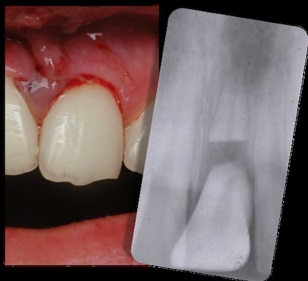

Tooth is Knocked Out

- Find the tooth.

- Hold by the crown part and rinse the root part with water. Do not rub, scrape, or touch the root part.

- Best to push the tooth back into the socket that it fell out of, trying to reposition the tooth exactly how it was before falling out. It needs to be put back in within 5-10 minutes. Bite down into towel or clothe to stabile. If unable to put back into place, the next best option is to place the tooth inside the mouth, under the lip or tongue to keep moist. Or spit into a cup to place tooth into. Or put into a cup of milk to take to the dentist. Some emergency kits may even be equipment with “SAVE A TOOTH” preservation kit.

- See a dentist ASAP, no longer than 24 hours.